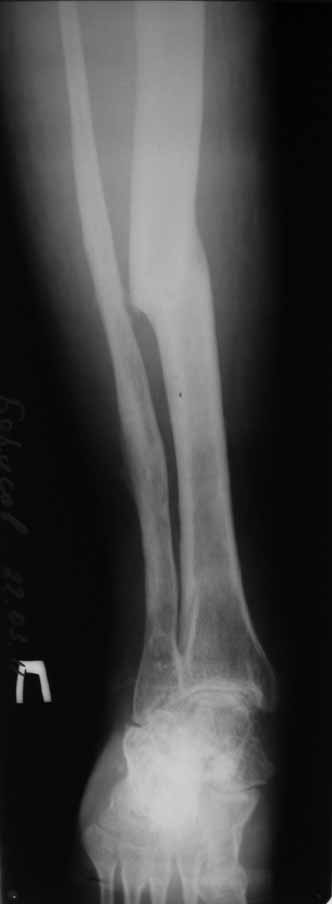

В анамнезе этапные операции по поводу устранения Coxa Vara, формирование артродеза коленного сустава, удлинения бедра. В данный момент беспокоит укорочение 7 см, эквинус стопы. Объективно: - местный статус виден на фото, сосудистых и неврологических расстройств нет. Обратился в консультативном порядке, настроен на удлинение голени в г.Волгограде. (со слов больного - не берут без санации очага на голени). Ваши предложения? Из кулуарных соображений - а не актиномикоз ли это? Иссечение рубцов+ VAC+ Стержень с аппаратом + микрососудистый трансплантат(?)

Ваш вопрос, коллега, вполне правомерен. В советское время те из нас, кто занимался костно-гнойной инфекцией видели достаточное количество подобных несчастных, кочующих из стационара в стационар. Своеобразный госпитализм приводил к тому, что люди тратили всю свою, как правило достаточно короткую жизнь, на лечение зачастую реально неизлечимых процессов. В данном случае имеющаяся рентгенологическая картина груботрабекулярной перестройки кости, сочетающаяся с участками склероза говорит, скорее всего, о том, что вся имеющаяся картина, дополненная чудесными фотографиями,вполне укладывается в клинику гематогенного остеомиелита, которым и страдает пациент с детства. Никакие санации, к сожалению, не приведут в данном случае к излечению, так как все имеющиеся рубцы являются зоной жизни этой самой инфекции. При продолжении лечения не исключено достаточно раннее развитие амилоидоза в этом случае. Мне кажется, что оптимальным было бы определить пациента в институт протезирования и протезостроения или в то учреждение, которое в регионе выполняет данную функцию. Специалисты помогли бы определиться с уровнем ампутации, являющейся, по сути, единственным способом разорвть порочный круг и дать пациенту возможность какой-то социальной адаптации. А в плановом порядке, насколько мне известно, можно добиться неплохого финансового обеспечения под протез конечности по квоте. Другого решения здесь нет. С уважением, Андрей Волна

Чтобы пытаться провести лечение данного пациента надо точно понимать - что хочет пациент? Какими усилиями с его и врачей стороны? В какой временной промежуток?. Предложение Андрея Волны возможно, если пациент уже ничего не хочет, или не возможно ему помочь по причине органной недостаточности - амилоидоз. Тогда, конечно, ампутация, протезирование. Возможно, на западе в том числе по экономическим причинам так и поступают. Но судя по литературе далеко не всегда. Эта тактика напоминает известное выражение "Есть человек, есть проблемы,..." ну и так далее. Если пытаться помочь пациенту, то гематогенный остеомиелит не настолько неразрешимая проблема. Хотя не понятно, почему удлинение за счет голени, при ложном суставе бедра. Я бы начал с попытки сращения бедренной кости, любыми возможными на взгляд лечащего хирурга методами (возможно придется их менять по ходу лечения или комбинировать). При мелких секвестрах удаление оных, но в первую очередь создать опорную конечность. Вторым этапом. Купирование гнойного процесса в тех очагах где он остался. При этом, кроме стандартных остеонекрэктомий с дренированием, можно и с VAC (мода вещь великая, а, может, и реально помогает, своего опыта, к сожалению, в применении современного VAC не имею, хотя, мне кажется, в основе это давно известные методы, изложенные у М.Кузина в "Гнойной хирургии"), кроме стандартных остеонекрэктомий необходима пересадка большого сальника в область гематогенного гнойного процесса. Пересадку можно сделать как свободным лоскутом, так и возвожна раскройка его в длинный кровоснабжаемый лоскут и с протягиванием под паховой складкой и распластыванием в зонах гнойных очагов бедра и голени. При наличии организационно нескольких бригад хирургов и подготовленных анестезиологов можно совместить оба этапа (операция может занять до 16 часов). Пересадка большого сальника в зону гематогенного гнойного очага в кости практически дает выздоровление или стойкую ремиссию ( проверено на полифокальных и монофокальных гематогенных остеомиелитах). Далее удлинять конечность в каком угодно месте, но я бы стал делать дистальнее, тем более что это может потребовать, во-первых, неоднократных остеотомий, во вторых, имеется потерянная иннервация малоберцовым нервом (говорится об укорочении 7 см и об эквинусе), и можно совместить удлинение с решением проблемы эквинуса. Это общий план. Надо принять во внимание, что по моему опыту это может потребовать до 8 лет перманентного оперативного лечения в худшем случае. Не все пациенты и врачи готовы к такому марафону. Но опять же по моему опыту, пересадка сальника в зону гематогенного патологического очага давала стойкую ремиссию. У меня был один пациент который после пересадки сальника через 3 года сломал голень с гематогенным очагом - криминальная травма- но гематогенный остеомиелит не обострился, а перелом голени срастался в обычные сроки в гипсе (4-6 мес). Но вернуться к теме ампутации можно на любом этапе. Кстати, надо будет при этом понять на каком уровне ампутировать. Ну и конечно, надо помнить о болезнях культей, в нашем случае это очень возможно (в Новокузнецком институте протезирования было даже отделение болезней культей, в том числе и гнойных). Это как в эндопротезировании суставов - решаем одну проблему, но можем получить другую. С уважением Ангельский А.А.

конечность опорна(!). Самая галвная жалоба - утомляемость, ноющие боли в области ТБС при длительном хождении, и укорочение. Пациент соматических жалоб не предъявляет.